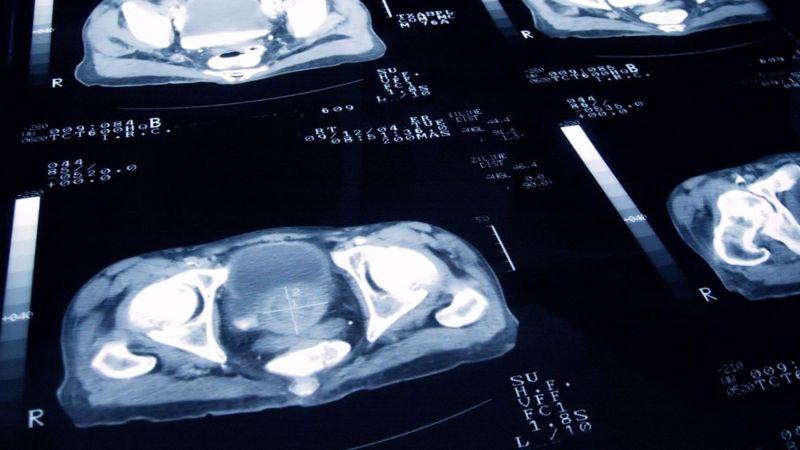

Los hombres que necesitan someterse a un tratamiento para el cáncer de próstata podrían recibir mucha menos radioterapia.

De acuerdo con la investigación, las dosis se pueden reducir en tres cuartas partes, lo que significa que 5 sesiones de radioterapia más altas son suficientes, en lugar de las aproximadamente 20 que se administran ahora.

Eso significa que miles de hombres podrían recibir dosis mayores de radioterapia (también conocida como radioterapia multihaz) en cada visita al hospital, pero en menos sesiones.

En el estudio, realizado a nivel internacional, participaron casi 900 hombres con cáncer de próstata de riesgo medio y que aún no se había propagado.

Los resultados mostraron que después de 5 años, el 96% de los hombres que recibieron 5 dosis altas de radioterapia estaban libres de cáncer, en comparación con el 95% que recibió al menos 20 dosis de radioterapia estándar.